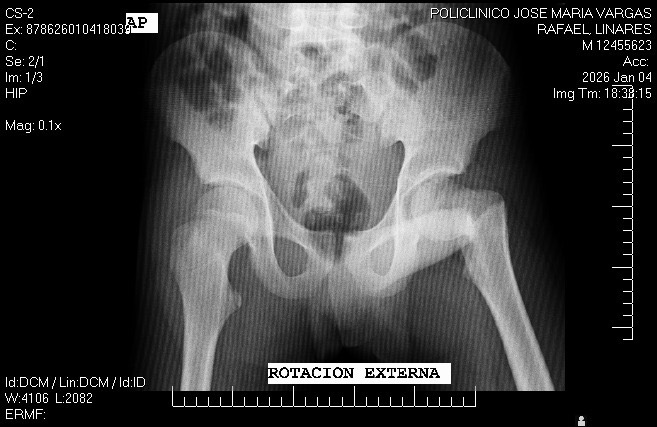

Mi sobrino Rafael Linares, de 14 años de Edad sufrió un accidente inesperado que le causó una lesión grave en la cadera. Los médicos han indicado que necesita una cirugía urgente para poder recuperarse y volver a caminar sin dolor.